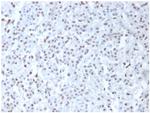

Wilm's Tumor 1 (WT1) (Wilm's Tumor and Mesothelial Marker) Polyclonal Antibody